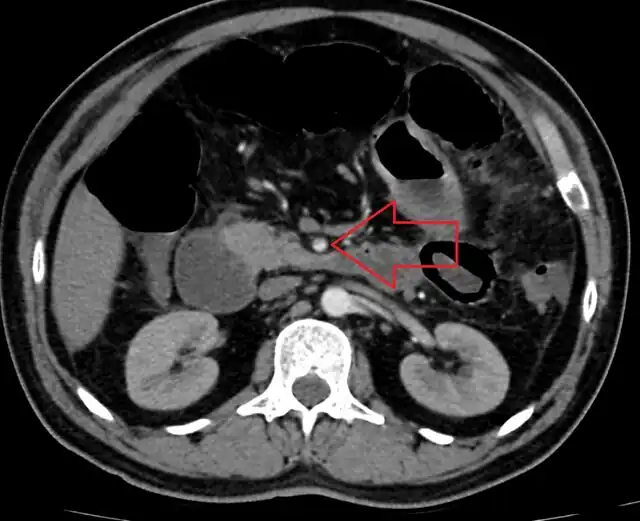

| Computed tomography (CT) showing dilated loops of small bowel with thickened walls (black arrow), findings characteristic of ischemic bowel due to thrombosis of the superior mesenteric vein. | |